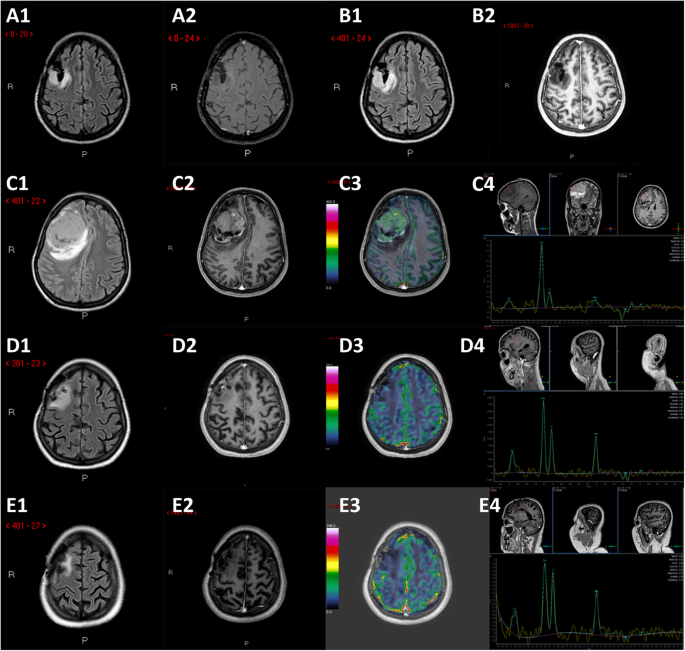

Fig. 1

Brain-MRIs. Legend: postoperative findings after Astrocytoma tumor (WHO grade II) resection in the right frontal lobe (not shown). A, axial FLAIR (A1) and contrast-enhances T1 (A2) images 12-months FU after first surgery demonstrate small residual tumor posterior to surgical cavity without any enhancing portions. B, axial FLAIR (B1) and contrast-enhances T1 (B2) obtained after 14 months shows minimal residual tumor enlarge without enhancement. C, axial FLAIR (C1), contrast-enhances T1(C2), corresponding DSC perfusion CBV map (C3) and Single-Voxel Spettroscopy (5 months after second-surgery): progression-disease with right-frontal heterogeneously enhancing mass (C2) with surrounding FLAIR signal hyperintensity (C1), elevated cerebral blood flow (C3) and abnormally elevated Cho/NAA ratio (C4), found to be a Glioblastoma (WHO grade IV). D, axial FLAIR (D1), contrast-enhances T1(D2), perfusion CBV map (D3) and Single-Voxel Spettroscopy (D4) 6 months after third surgery: gross total resection of enhancing tumor (D2) with minimal surrounding nonenhancing white matter signal abnormality (D1) and focal dubious rCBV elevation (D3). E, axial FLAIR (E1), contrast-enhances T1(E2), perfusion CBV map (E3) and Single-Voxel Spettroscopy (E4) 12 months after third-surgery: substantial stability of the gross total resection of enhancing tumor (E2) with persistence of both minimal surrounding nonenhancing white matter signal abnormality (E1) without focal rCBV elevation (E3)

A 29-year-old healthy left-handed woman, admitted to another institution after the appearance of a focal motor epileptic seizure, underwent subtotal surgical removal of a right frontal WHO grade II Astrocytoma in June 2015 (Fig. 1, A1–2). The lesion remained stable at the following six-months follow-up MRI studies until October 2017, when the patient underwent a new brain surgery for neuroradiological findings of locoregional recurrence (Fig. 1, B1–2), without any clinical worsening. Histological investigations confirmed a WHO Grade II Astrocytoma (MGMT promoter methylated, IDH1-mutated; absence of 1p/19q deletion; ki-67 index: 4%; Fig. 2, A1–3). The Karnofsky Performance Status (KPS) score at discharge was 100. Five months after the second surgery the patient presented a sudden clinical worsening, with the appearance of left hemiparesis and focal motor epileptic seizures affecting the left upper limb. A new Brain MRI documented a massive recurrence of the right frontal lesion with evident signs of grading change (Fig. 1, C1–4). This motivated the third surgery performed in April 2018, which led to a subtotal resection. Histological investigations revealed a WHO grade IV (MGMT promoter methylated, IDH1-mutated; absence of 1p/19q deletion; ki-67 index: 60%; Fig. 2, B1–3). The patient was initially treated accordingly to the protocol recommended by Stupp et al. [5] with concomitant radiation therapy (2 Gy given five days per week for six weeks, total dose: 60 Gy) and chemotherapy with Temozolomide (75 mg/m2 per day for six weeks), followed by adjuvant chemotherapy with Temozolomide (200 mg/m2 for 5/28 days). Unfortunately, the adjuvant chemotherapy with Temozolomide was early suspended after two cycles because of grade III blood toxicity with pancytopenia. In September 2018, a right cervical lymph node swelling appeared. An ultrasound of the neck showed some lymph nodes increased in size (maximum diameter of 3.5 cm) with pathological structure in the right lateral cervical site (Fig. 3, A1–2). A needle biopsy was performed and, according to the immunohistochemical, biomolecular and histological results, confirmed the presence of an extracranial metastatic localization of GBM (Fig. 2, C1–3). A thoracic and abdominal CT scan ruled out further diffusion to other sites, and a brain MRI didn’t show any sign of progression of the primary lesion. Locoregional radiotherapy (6 Gy given for five consecutive fractions, total dose: 30 Gy), was performed leading to a complete remission of the 18F-FDG uptake in the right lateral cervical region at the five months follow-up. In addition, a second-line chemotherapy with Procarbazine-Lomustine was started, but it was stopped after the second cycle, because of grade III blood toxicity with pancytopenia. About two months after the last radiotherapy treatment, the patient complained of the appearance of severe diffuse drug resistant arthralgia and back pain, without any worsening at neurologic examination. A whole body 18F-FDG PET/CT scan showed multiple increased 18F-FDG uptake areas involving ilium bilaterally and the proximal third of the femurs (SUV max = 25), scapula and humeral head bilaterally (SUV max = 22), sternum (SUV max = 20), some ribs, some vertebrae and the sacrum (SUV max = 15; Fig. 3, B). None of the 18F-FDG uptake areas correlated with significant structural alteration on CT scan. Pelvis MRI demonstrated signal alteration areas compatible with GBM metastatic bone infiltration (Fig. 3, C1–5). Based on PET images and MRI, a CT guided biopsy was performed at the right iliac wing (Fig. 3, D) and the histopathological examination confirmed the presence of secondary bone localizations of GBM (Fig. 2, D1–3). In the face of this diffusion, brain-MRI documented stability of the brain disease for 14 months (Fig. 1, D1–4, E1–4; Fig. 3, A1) and no clinical or radiological signs of progression were discovered in the irradiated lymph node site for approximately 1-year. About 12 months after the appearance of the first metastatic site, the patient was hospitalized in a Hospice with a KPS score of 70 where died for extracranial progression of the disease and subsequent sepsis at the age of 33-years. Figure 4 summarizes the timeline of the patient’s history.